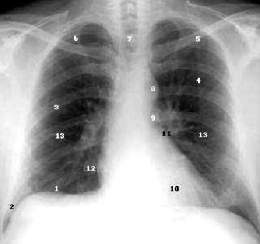

Radiografía de tórax. Consiste en la obtención de una imagen radiológica del tórax. Esta imagen surge de la interposición de la zona anatómica a estudio entre una fuente emisora de radicación ionizante (rayos X) y una placa fotográfica o registro fotográfico digital.

El tórax es la zona anatómica delimitada por el cuello y el abdomen.